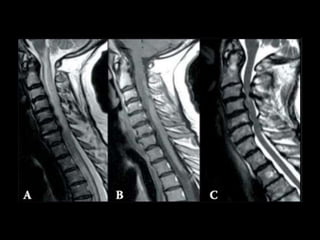

COLUNA

 Coluna cervical

 Coluna torácica

 Coluna lombar

 Coluna sacral

 “Coluna Lombo-sacra”

RM COLUNA

CERVICAL/TORÁCICA/LOMBAR

 Hérnia de disco

 Canal medular